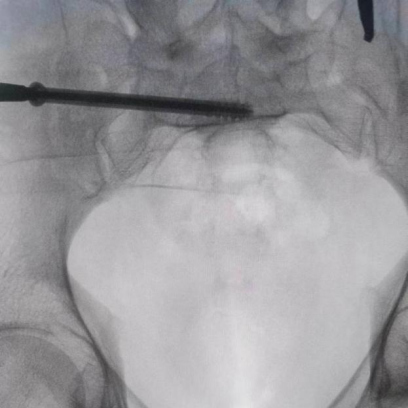

圖為透視下見置入的骶髂螺釘,位置、長度精準(zhǔn),無絲毫偏差